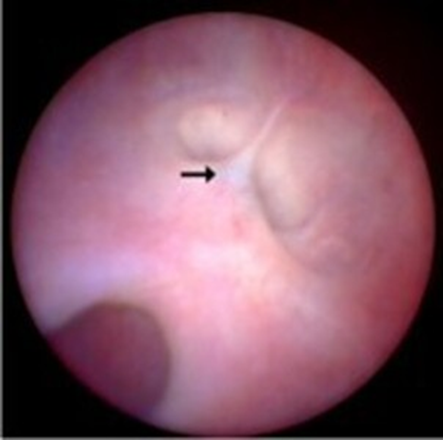

Advancing through the urethra into the bladder, a large cystic structure originating from the left ureterovesical junction was visualized at the trigone. The right ureterovesical junction appeared anatomically normal, with an adequate ureteral jet. Correction was achieved with a 5 Fr, 36 cm endoscopic scissor, creating an opening in the cystic structure that allowed release of ureteral flow and removal of an obstructive ureterolith. The calculus was extracted using a semi-rigid stone retrieval forceps (4.1 Fr, three-pronged, 37 cm length) introduced through the urethral channel. Restoration of ureteral flow was confirmed by direct visualization of the ureteral jet from the left ureterovesical junction. During the same procedure, correction of the persistent paramesonephric ligament was also performed via endoscopic sectioning. Postoperative therapy included dipyrone 25 mg/kg tid, meloxicam 0.05 mg/kg sid, and amoxicillin–clavulanic acid 25 mg/kg bid. The patient recovered uneventfully without postoperative complications. Intraoperative images are shown in Figure 4.

Figure 4: A) Ureterocele at the left ureteral orifice (ã), adjacent to the right ureteral orifice (¨), located at the trigone, visualized from the urethral canal. B) Visualization of the ureterocele (ã) forming a prominent protrusion at the trigone during bladder distension; right ureter with normal slit-like orifice (¨). C) Use of endoscopic scissors (Ò) for transection and enlargement of the ureteral orifice, correcting the ureterocele (ã). D) Incision of the ureterocele, enabling visualization of a ureterolith (¿). E) Removal of the ureterolith (¿) with a trident endoscopic forceps (t). F) Surgical incision of the ureterocele (ã) performed with endoscopic scissors (Ò).